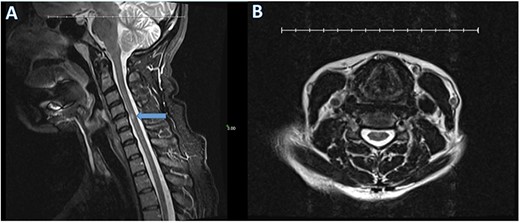

During telemedicine evaluation, she discussed her fall. She had not understood the significance of her trauma and experienced symptoms consistent with postconcussive syndrome (PCS), including persistent problems with memory, concentration and decision making. Without telemedicine, she would have been advised to see a neurologist for brain and optic nerve MRI, visual evoked potentials, and lumbar puncture with cerebrospinal fluid analysis (CSF) to work up multiple sclerosis. A non-contrast T2-weighted cervical MRI from 1 month before neurosurgical evaluation revealed a 4 mm area of hyperintensity within the spinal cord at the C4–C5 level consistent with previous spinal cord injury (Fig. 1). Anteroposterior (AP), lateral and flexion/extension radiographs were recommended to assess for cervical instability, though these were not possible with COVID-19 restrictions. She was counseled regarding risks and benefits of future surgical decompression and fusion to prevent progression and stabilize the cervical spine, though surgery is unlikely to return function. After 1 year of relative clinical stability without her cervical collar, it was not deemed necessary to restart its application. Six weeks after evaluation she continued to experience neck pain with arm weakness and numbness without symptom progression.

T2-weighted sagittal (A) and axial (B) cervical spine MRI reveals a 4 mm hyperintense area within the spinal cord at the C4–C5 level (arrow) and a disc bulge without spinal cord deformity.